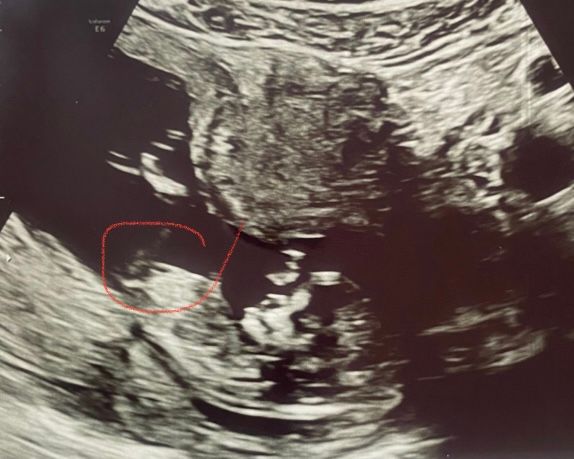

Девочки, как думаете кто? Мне кажется девочка, половой бугорок прямо, фото узи от 12,4 недель.

Скоро сама узнаю на втором скрининге, но не терпится😀

Я вижу девочку)

Мне кажетсямальчик) на 1 скрине у меня не увидели и я сделана тест по крови) потом уже и доктор подтвердил на следующем узи)

Лучше не гадать , мне в 13 недель сказали мальчик 100% , а 17 недель сказали девочка 100 % , потом было ещё 2 УЗИ и подтвердили девчулю